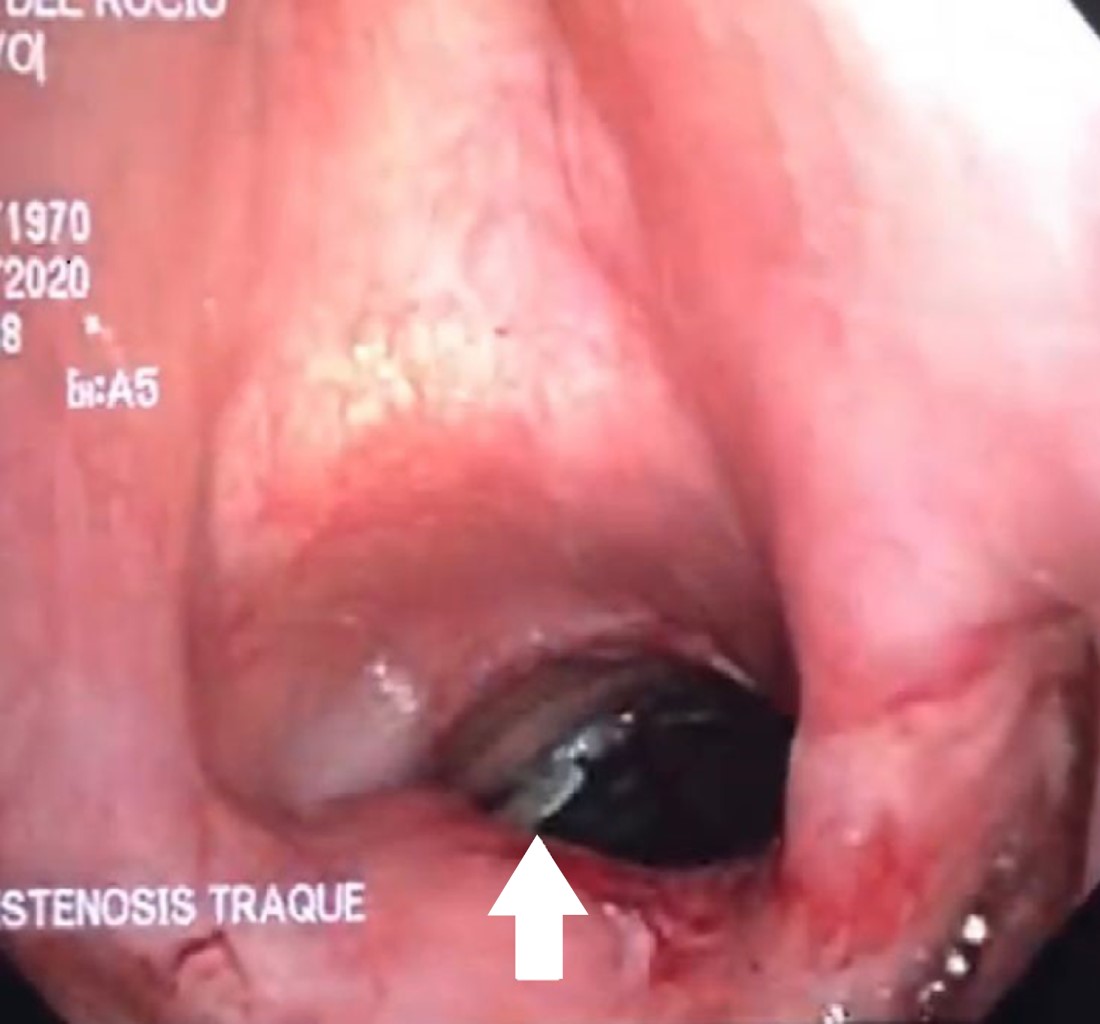

Femenino de 62 años con antecedente de diabetes mellitus e hipotiroidismo. Inició con síntomas sugestivos de COVID-19 el 21 de octubre de 2020, acudió a hospital general ocho días después con datos de insuficiencia respiratoria, se realizó tomografía computarizada y prueba de hisopado PCR para SARS-CoV-2 con resultado positivo; se decidió intubación orotraqueal. Adecuada evolución y extubación a los 10 días con mal manejo de secreciones y estridor laríngeo, con necesidad de reintubación 24 horas posteriores. Segunda extubación por mejoría clínica a los cuatro días; sin embargo, se agregó disfagia, por lo que se realizó esofagograma con evidencia de fístula traqueoesofágica. Se colocó endoprótesis esofágica y sonda de gastrostomía por el servicio de endoscopia. Presentó evolución tórpida y un mes después desarrolló deterioro neurológico y desaturación requiriendo nueva intubación orotraqueal. Se programó fibrobroncoscopia de revisión por Servicio de Cirugía de Tórax del INER una semana después por sospecha de estenosis traqueal, observando secreciones espesas y prótesis esofágica migrada en porción proximal de tráquea (Figura 1). Se identificó fístula traqueoesofágica (Figura 2) en pared membranosa de la tráquea de 4 cm, se realizó traqueostomía percutánea a nivel del cuarto anillo traqueal dejando rama distal de la cánula a 1 cm de carina principal. Al cabo de 10 días se retiró apoyo con ventilación mecánica. Se egresó a domicilio el 25 de enero de 2021 con nutrición enteral.